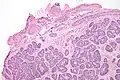

| Micrograph of a Sertoli cell nodule. H&E stain. | |

Sertoli cell nodules are unencapsulated nodules that consist of:[2][3][4]

- cells arranged in well-formed tubules (that vaguely resemble immature Sertoli cells), with

- bland hyperchromatic oval/round nuclei that are stratified, and

- may contain eosinophilic (hyaline) blob in lumen (centre).

Micrograph of a Sertoli cell nodule. H&E stain.